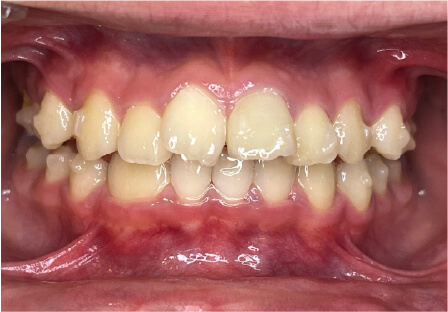

叢生の症例

8歳

/

女性

相談内容

前歯がでている、前歯が噛み合っていない

カウンセリング・診断結果

上下叢生、顎が狭いのでクリアコレクトで拡大配列+トレーニングで進めてく

治療内容・方法

全額アライナー矯正 クリアコレクト

術後の経過・現在の様子

リンガルアーチ使用

治療のリスク

痛み・歯根吸収・歯肉退縮・虫歯・後戻り

費用・治療期間

924,000円、8ヶ月

トレーニングなど